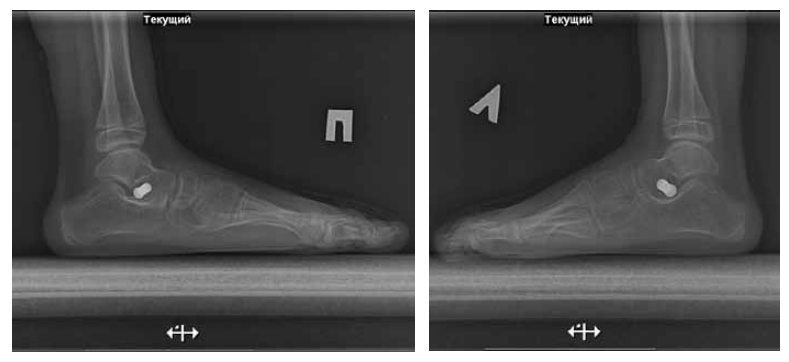

Patient Ch., 8 years old. Diagnosis: cerebral palsy with spastic diplegia and severe talipes equinoplanovalgus. The patient was admitted to the clinic with complaints of gait abnormality, deformity of the feet, and difficulty in wearing shoes (Fig. 2).

Fig. 2. Radiographs of the feet under load before the surgery: a — frontal view; b, c — lateral views